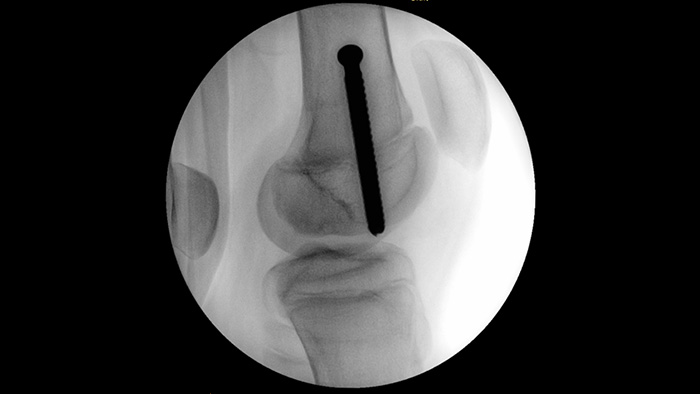

MetalSmart excluye automáticamente los artefactos metálicos causados por implantes metálicos para proporcionar una mayor calidad de imagen y un control de dosis eficiente durante procedimientos de ortopedia y para los pacientes con implantes metálicos, en comparación con los sistemas sin exclusión de metales. BodySmart promueve la adquisición de imágenes en el primer momento y la eficacia de la dosis al adaptar automáticamente el campo de medición al área de interés.